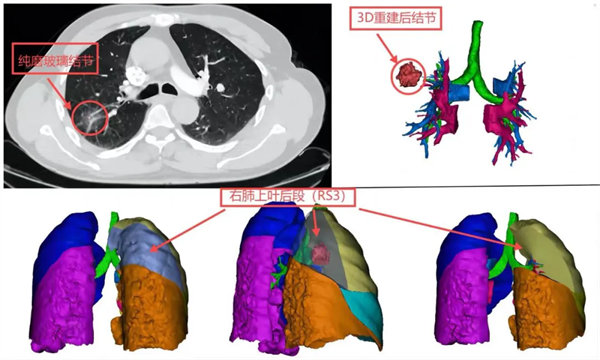

患者李先生(化名)是一位55歲男性患者,在體檢時查出右肺上葉后段有一個約26mm純磨玻璃結節,收住我院胸外腫瘤外科,經過對病人情況的詳細檢查,通過跟患者的多次溝通和對病情的研究,胸外腫瘤外科團隊在主任陳瑜的帶領下經過深入討論與精心準備,決定為患者采取單孔胸腔鏡肺段切除術。

手術由科室副主任吳明君主刀,在張鵬、張寶軍、楊永濤等醫師配合下,為患者行單孔胸腔鏡下右肺上葉后段切除術(S2),經過兩個小時手術,精準的切除了病灶,術后病理檢查結果為微浸潤腺癌,此次手術切除范圍更小,更精準,后期肺功能保留更好,又達到根治,術后患者恢復良好,已康復出院。